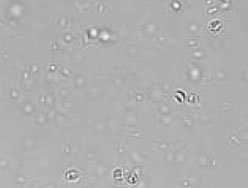

![]() 図4 クリプトスポリジウム ショ糖遠心沈殿浮遊法 |

| 〔症例4〕25歳の男性 5週間のネパールとチベット旅行中から下痢と腹痛があり1999年4月15日に当院内科を受診した。 受診時の検査結果は、CRPが強陽性で血液検査のデータはやや高値であるが、生化学は基準値内であった(表4)。 ショ糖遠心沈殿浮遊法でクリプトスポリジウムのオーシストを検出した。 |